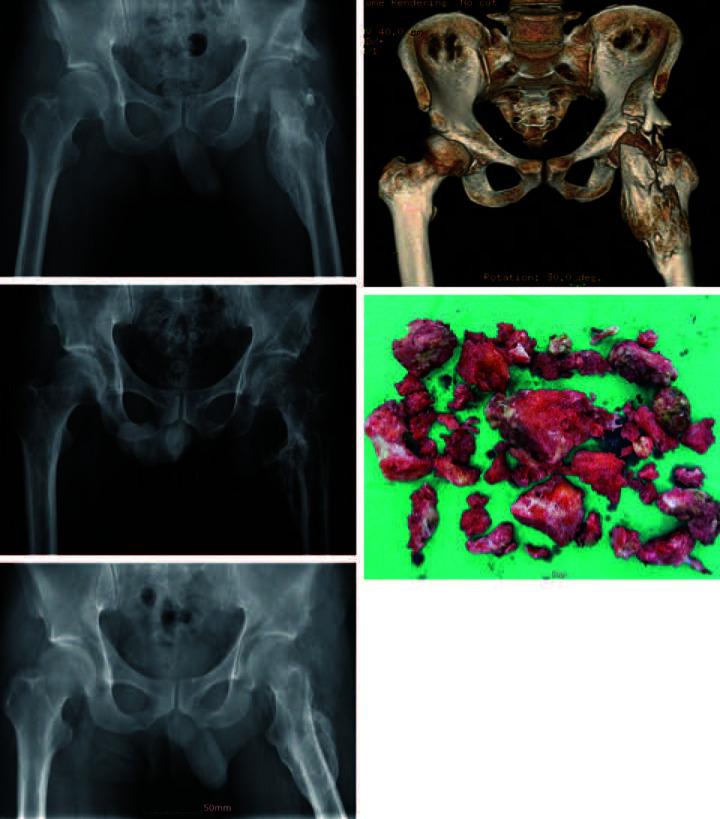

Purpose: Resection remains the most reliable treatment for established heterotopic ossification, despite questions regarding its effectiveness due to the potential for complications. This study evaluated the clinical outcomes and complications of neurogenic heterotopic ossification (NHO) resection in stroke patients' ankylosed hips.

Materials and methods: We retrospectively analyzed nine hip NHO resections performed on seven patients from 2010 to 2018. The pre- and postoperative range of motion of the operated hip were compared. Analysis of postoperative complications, including infection, recurrence, iatrogenic fracture, and neurovascular injury was performed.

Results: The mean operative time was 132.78±21.08 minutes, with a mean hemoglobin drop of 3.06±0.82 g/dL within the first postoperative week. The mean duration of postoperative follow-up was 52.08±28.72 months for all patients. Postoperative range of motion showed improvement from preoperative. Flexion and external rotation (mean, 58.89±30.60° and 16.67±18.03°, respectively) showed the greatest gain of motion of the operated hip joint. Postoperative infections resolved in two cases through surgical debridement, and one case required conversion to total hip arthroplasty due to instability. There were no recurrences, iatrogenic fractures, or neurovascular injuries.

Conclusion: Resection is a beneficial intervention for restoring the functional range of motion of the hip in order to improve the quality of life for patients with NHO and neurological disorders. We recommend performance of a minimal resection to achieve a targeted functional arc of motion in order to minimize the risk of postoperative complications.